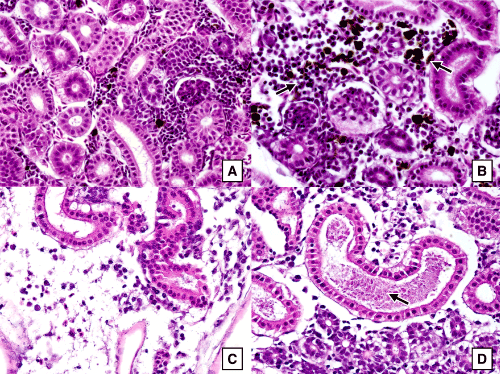

| Figure 3: Sections of kidney tissues of coho salmon fry (three months old) stained with H&E and magnified 400X showing: (A) healthy kidney tissues of coho salmon from the negative control group, (B) kidney tissues of an intraperitoneally infected fish with melanomacrophage hyperplasia, (C) kidney tissues of an intraperitoneally infected fish with tubular degenerative changes and edema within the renal interstituim, (D) kidney tissues of an intraperitoneally infected fish with renal tubular degeneration and proteinaceous casts in the tubular lumen (arrow) |